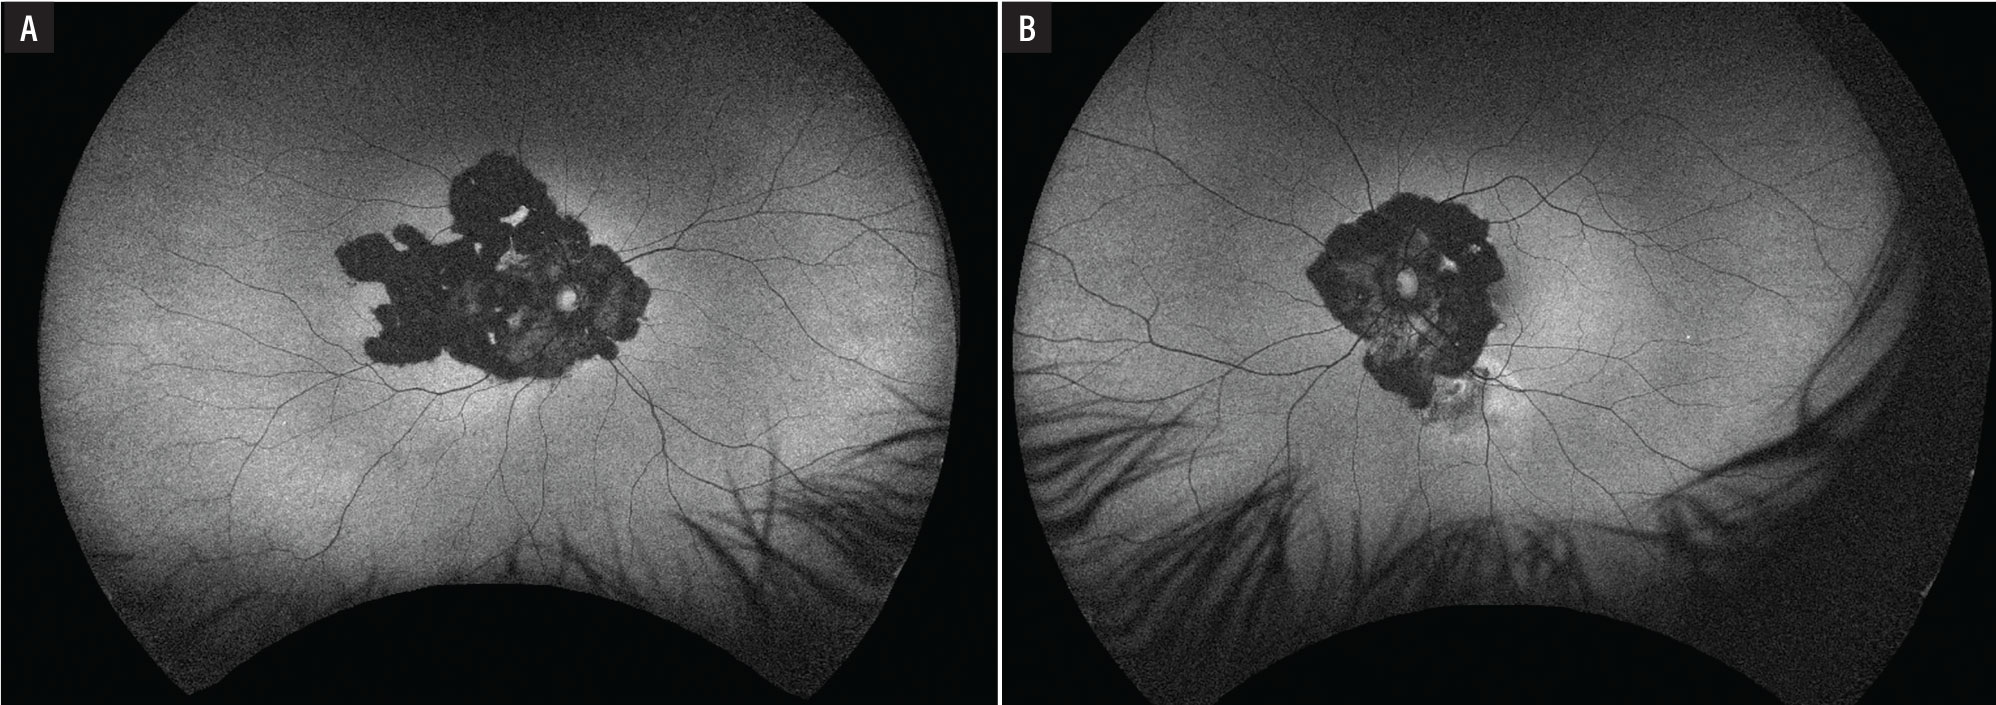

Fundus autofluorescence demonstrated dense hypoautofluorescence in the area of chorioretinal atrophy in the right eye (Figure 3A) and dense hypoautofluorescence in the area of chorioretinal atrophy with an adjacent area of hyperautofluorescence along the inferior arcade in the left eye (Figure 3B).

Fluorescein angiogram showed a large window defect in the area of chorioretinal atrophy with interspersed hypofluorescence from blockage due to hyperpigmentation and hyperfluorescence from the choroidal vasculature of the right eye (Figure 4A) and a similar pattern of fluorescence in the area of chorioretinal atrophy with an area of late leakage along the inferior arcade concerning for disease activity in the left eye (Figure 4B).

Figure 3. Fundus autofluorescence reveals dense hypofluorescence in both eyes with a leading edge of hyperfluorescence in the left eye (B) concerning for activity. |

Figure 4. A) Fluorescein angiogram in the right eye showed a window defect with inactive choroiditis. B) The left eye demonstrated a window defect with an area of active leakage along the inferior arcade. |